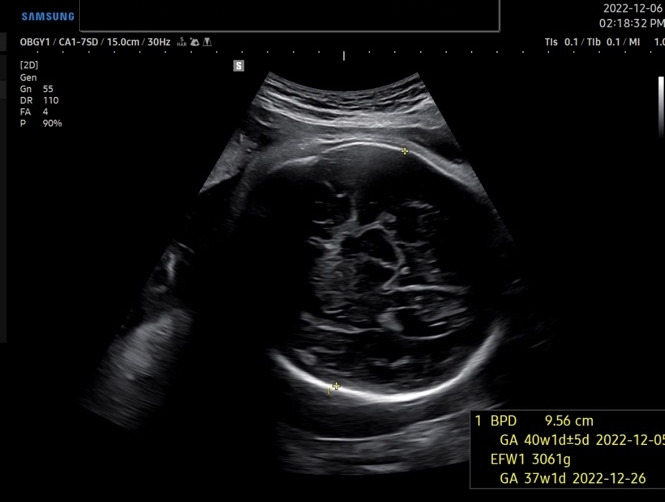

2주 만에 뵙는 주치의 선생님, 오늘도 아기가 주수에 맞게 잘 크고 있는지 초음파로 아기의 이곳저곳을 확인했다. 한 가지 반갑지 않은 소식은 아기의 머리가 계속 주수보다 크다는 건데, 이번에 잰 수치로는 3~4주가량 머리가 컸다. 몸통은 주수보다 작은데, 우리 써니 얼마나 똑똑하려고 머리가 큰 거니..

KakaoTalk_20221215_143326615.jpg 벌써 머리 직경이 9.56cm, 40주 1일 크기다...

남편은 머리가 정말 많이 큰지 다시 한번 되물었고, "평균보단 큰 편이에요 ^^;;"라는 대답이 돌아왔다.